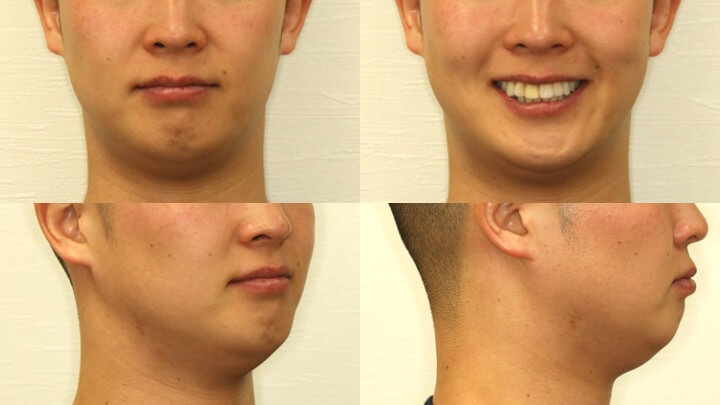

症例紹介

上の歯が一本奥に入っていて笑った時に気になる

下の前歯がガタガタ、歯肉が下がっている部分がある

患者様は笑った時に前歯が綺麗に並んでいないことを主訴として、当院を受診されました。

骨格性2級 ドリコフェイシャルタイプ

Angle 2級 前歯部叢生

本症例では、上下の前歯にガタガタ(叢生)があるだけでなく、噛み合わせの平面(咬合平面、スピーの湾曲)が強く傾いている状態でした。

約8ヶ月の治療により、前歯部のガタガタ(叢生)が改善され、噛み合わせの平面(咬合平面、スピーの湾曲)も改善しました。

咬合平面の改善により、左右均等に噛むことができ、犬歯による顎の誘導も適切に機能しています。歯軸が整直したことから後戻りの可能性が少ない噛み合わせになっています。

見た目だけでなく、噛みやすさと安定性を重視した治療結果が得られた症例です。